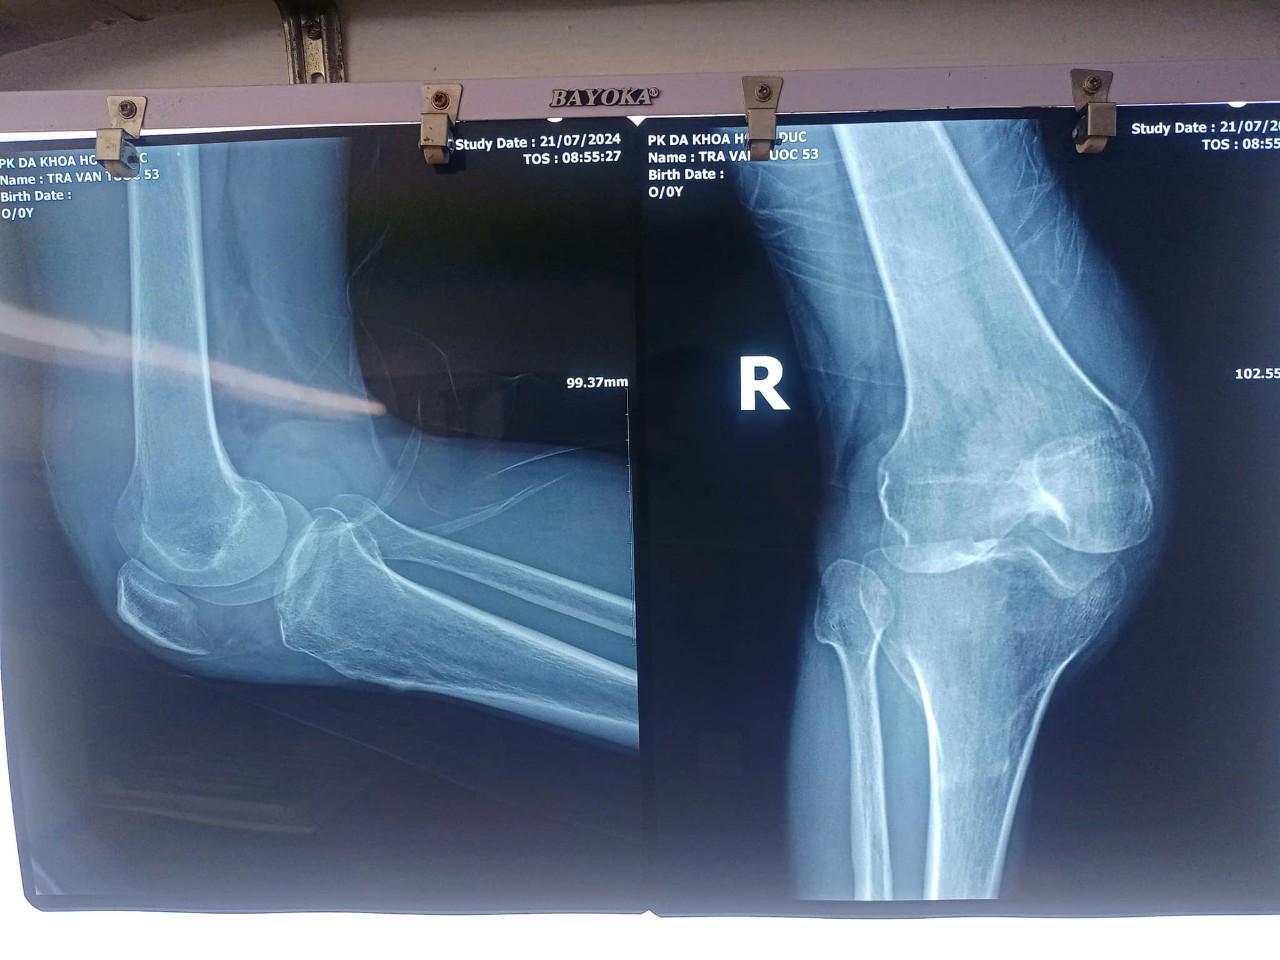

Vào ngày 21/07/2024, chuyên khoa Cơ - Xương - Khớp (CXK) của PKĐK Hồng Đức đã tiếp nhận một trường hợp bệnh nhân trong tình trạng khớp gối phải sưng nóng, đỏ và đau tới mức vận động chân bị co giật.

Bệnh nhân là ông Trà V.T (53 tuổi - sinh sống tại huyện Trần Văn Thời, tỉnh Cà Mau) đã khám và điều trị ở các cơ sở y tế khác nhưng không khỏi, vẫn trong tình trạng đau nhức khớp gối kèm theo sốt và phải di chuyển bằng xe lăn.

Các y bác sĩ của PKĐK Hồng Đức đã phối hợp cùng cố vấn chuyên môn CXK là Tiến sĩ - Bác sĩ nội trú Nguyễn Thị Hiền - Khoa CXK Bệnh viện Bạch Mai đưa ra phương hướng điều trị cho bệnh nhân (đây cũng là hoạt động hỗ trợ chuyên môn thường xuyên của PKĐK Hồng Đức). Kết hợp với hội chẩn của chuyên gia, các y bác sĩ PKĐK Hồng Đức đã rút dịch giải áp, xét nghiệm dịch và kê đơn thuốc, tư vấn chăm sóc cho bệnh nhân. Bệnh nhân cũng được hẹn ngày tái khám.